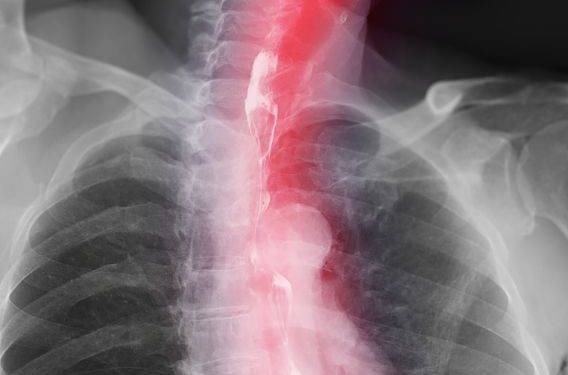

When a tumor is located in the esophagus, health professionals use a variety of tests to determine how far the cancer has spread, a process called staging. In addition to a physical examination, a doctor may order a chest X-ray, a CT scan of the neck and throat, an endoscopy, or a biopsy of the esophageal tissue. Blood tests may check for anemia, which can occur if the cancer has caused a lot of bleeding in the esophagus, and for abnormal liver enzymes, which indicate that the cancer may have spread to the liver.